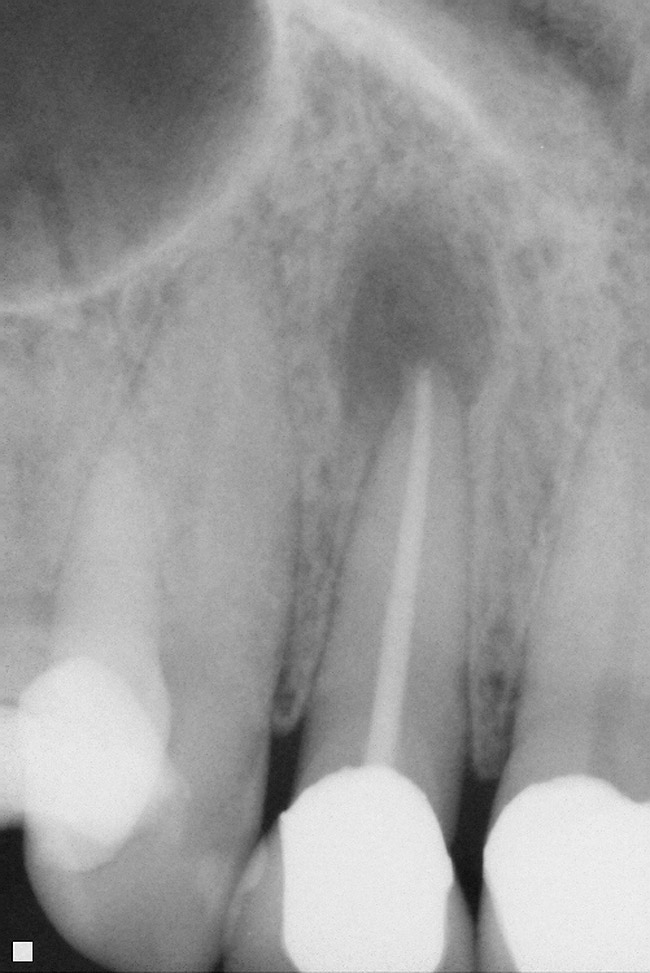

Figure 12  ENDODONTIC AND ESTHETIC PARAMETERS A tooth with a periapical radiolucency > 5 mm significantly decreases the success rate of endodontic therapy.

Figure 12